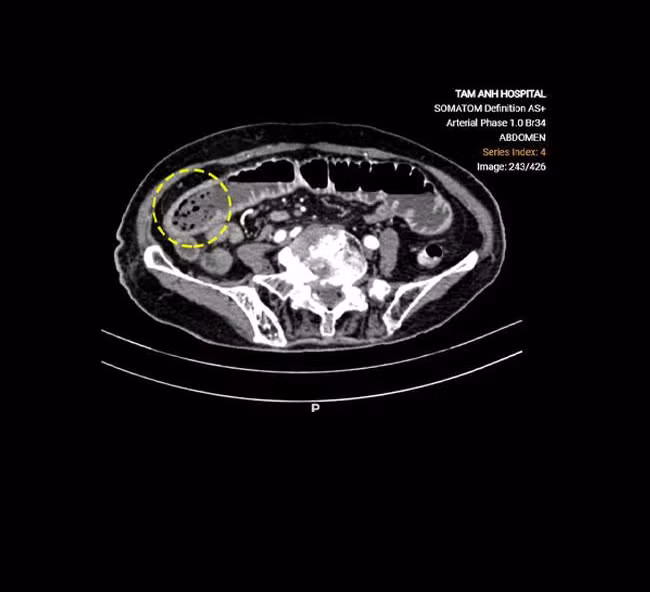

ThS.BSCKII Lê Văn Lượng, Khoa Ngoại tổng hợp, cho biết phim chụp X-quang ổ bụng của cụ Sinh phát hiện mức nước-hơi (tình trạng dịch và khí bị ứ trệ trên các quai ruột tắc giãn tạo ra các hình ảnh trên phim X-quang chụp bụng với mức nước phía dưới và hình hơi hình vòm phía trên). Phim chụp CT thấy khối bã thức ăn làm đoạn giữa ruột non giãn nghiêm trọng 4,4 cm, gây tắc ruột cơ học.

Khối bã thức ăn của cụ Sinh trên phim chụp CT - Ảnh BVCC

Bác sĩ Lượng cho biết tắc ruột có nhiều nguyên nhân phổ biến như thoát vị, dính ruột sau mổ, lồng ruột hoặc có khối u ruột. Cụ Sinh bị tắc ruột do bã thức ăn hình thành trong dạ dày không tiêu hóa hết và tích tụ tại ruột non, là nguyên nhân hiếm gặp, chỉ chiếm 0,4-4% tổng số ca tắc ruột.